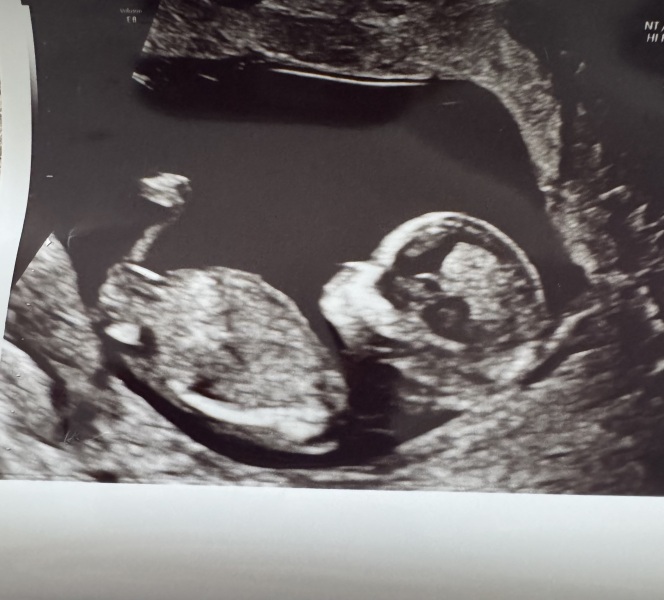

Hi, this is my 12+1 scan, would love to hear people's predictions on gender based on nub theory! I'm not sure if I'm looking at the nub or a leg. Will confirm when we find out on a few weeks time!

Hey would anyone be able to tell mine , I don’t have a clue what I’m looking at 12 weeks and 6 days